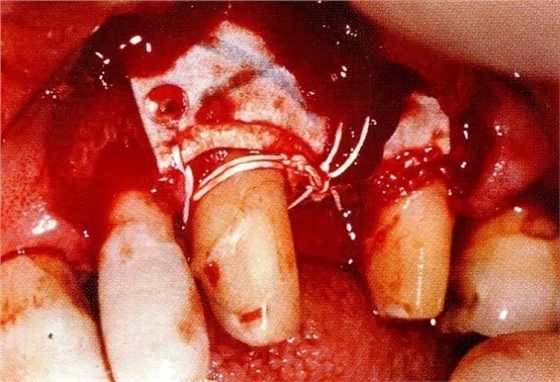

▲圖8-4,5為了確保足夠空間實(shí)現(xiàn)更好的再生,使用了2張鈦強(qiáng)化型gore-tex膜。

▲圖8-6通常,會(huì)將覆膜通過縫合線固定在牙齒上,但是,此情況下,使用了鑷子將覆膜進(jìn)一步往根尖側(cè)固定。